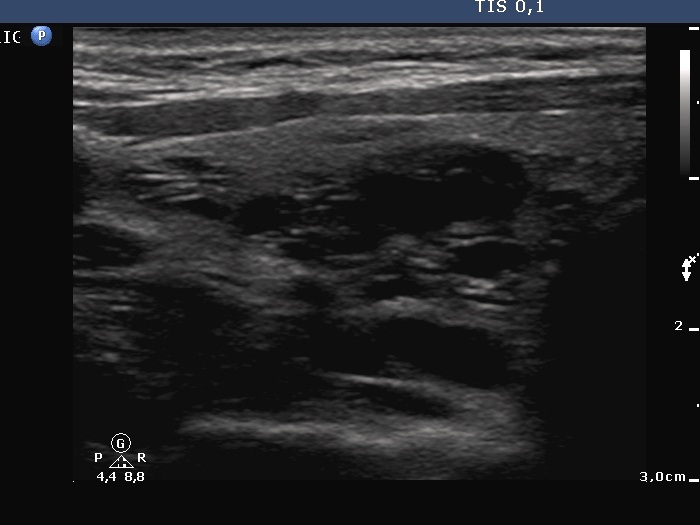

First examination (first row of sonographic images):

Clinical presentation: A 33-year-old woman was referred for evaluation of typical complaints suggesting hyperthyroidism.

Palpation: Both lobes were enlarged.

Functional state: hyperthyroidism (TSH undetectable, FT4 42.2 pM/L, FT3 above 46 pM/L).

Ultrasonography. The thyroid was diffusely hypoechogenic. The vascularization was increased. The left thyroid was significantly more inhomogeneous than the right lobe. Compare the first two index pictures in the first row with the third and fourth one, right and left lobe, respectively.